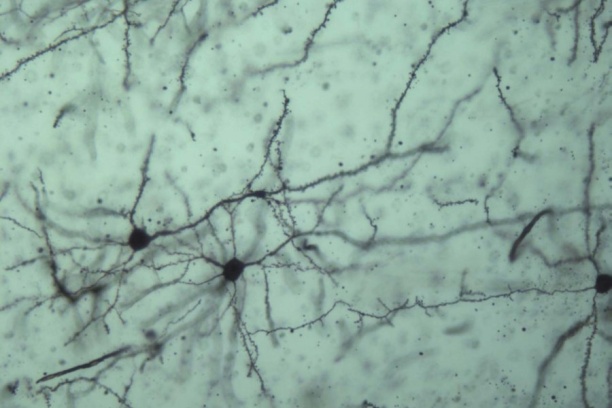

Over the past decade a novel class of neuromodulatory lipids, including N-arachidonylethanolamine (anandamide) and 2-arachidonoylglycerol (2-AG), that activates neuronal cannabinoid receptors has been the focus of intense research in neuroscience. These molecules are arachidonic acid derivatives produced by neurons and glia. These compounds act at the same site as the active constituent of cannabis sativa, Δ9-tetrahydrocannabinol (THC), and are termed endogenous cannabinoids (endocannabinoids; eCBs). Production of eCBs is driven by calcium influx secondary to strong neuronal depolarization or burst firing, and activation of some Gq-coupled neurotransmitter receptors and glucocorticoid receptors. eCBs are important retrograde modulators of synaptic signaling at central synapses.

The primary role of endocannabinoids such as 2-AG is retrograde synaptic suppression. Upon neuronal depolarization or Gq-coupled receptor activation, 2-AG is synthesized and released. It diffuses to presynaptic axon terminals where it activates CB1 receptors. Activation of CB1 receptors causes a decrease in neurotransmitter release. CB1 receptors are located on both GABAergic and glutamatergic axon terminals synapsing onto principle neurons. CB1-mediated synaptic suppression can be transient or long-lasting depending on specific pre- and post- synaptic activity levels.